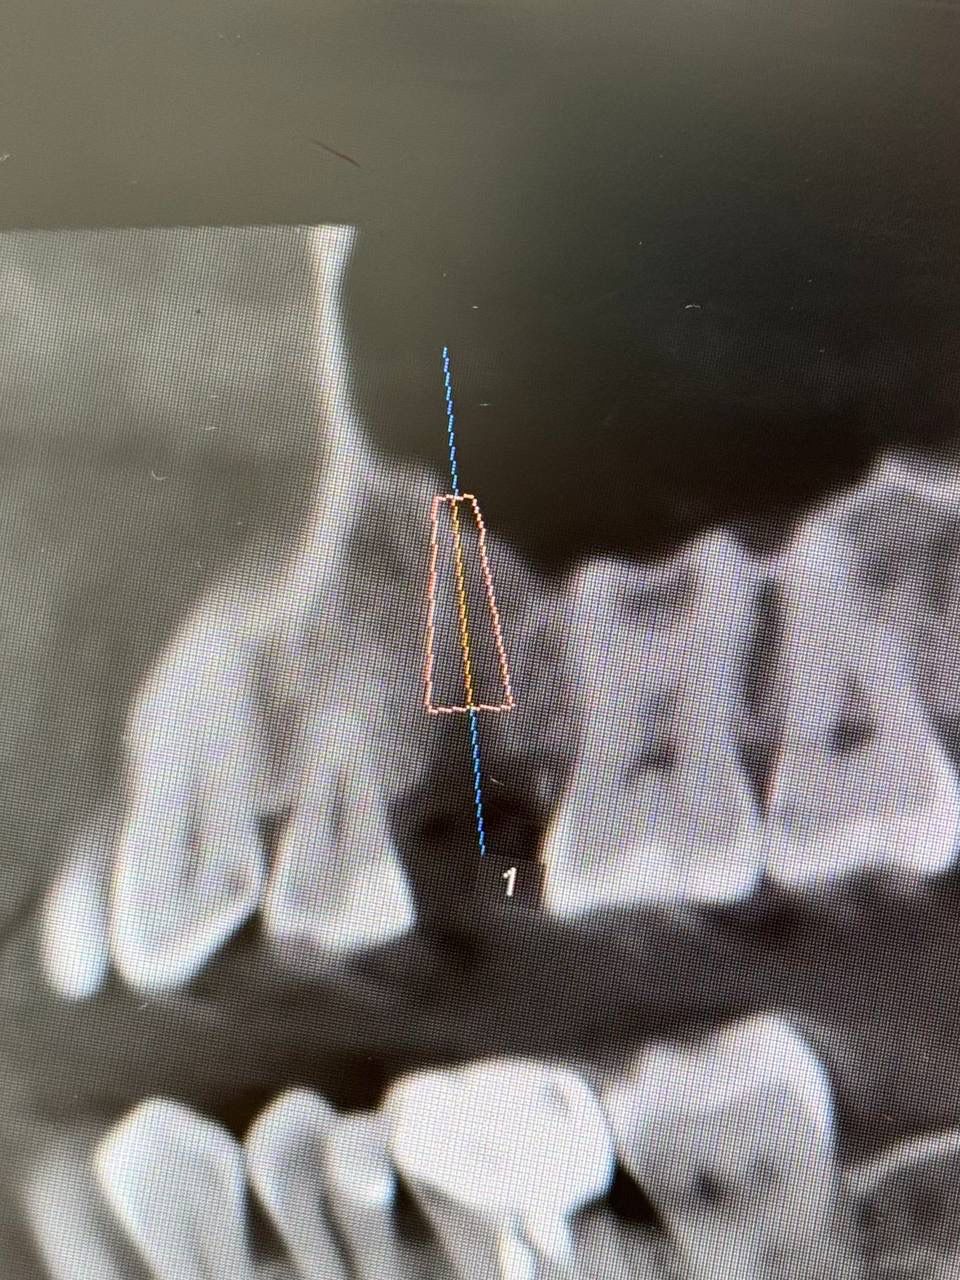

Установка импланта — Исламов Л.А.(10.11.2025)

Установка импланта, подшит трансплантат с бугра( для увеличения объема мягких тканей), установлен формирователь десны

Установка импланта